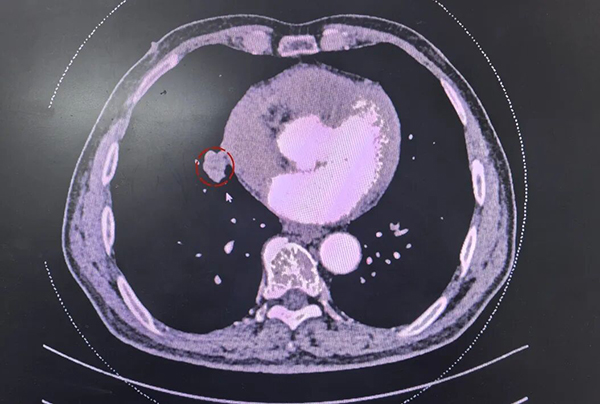

胸外科主任张雪冬接诊并为老人安排住院,完善相关检查,增强CT显示,老人右中肺存在一枚约2.8厘米的实性肿块,靠近肺门。经综合评估,老人的心肺功能及全身状况达标,无手术禁忌,可耐受单孔胸腔镜手术治疗。